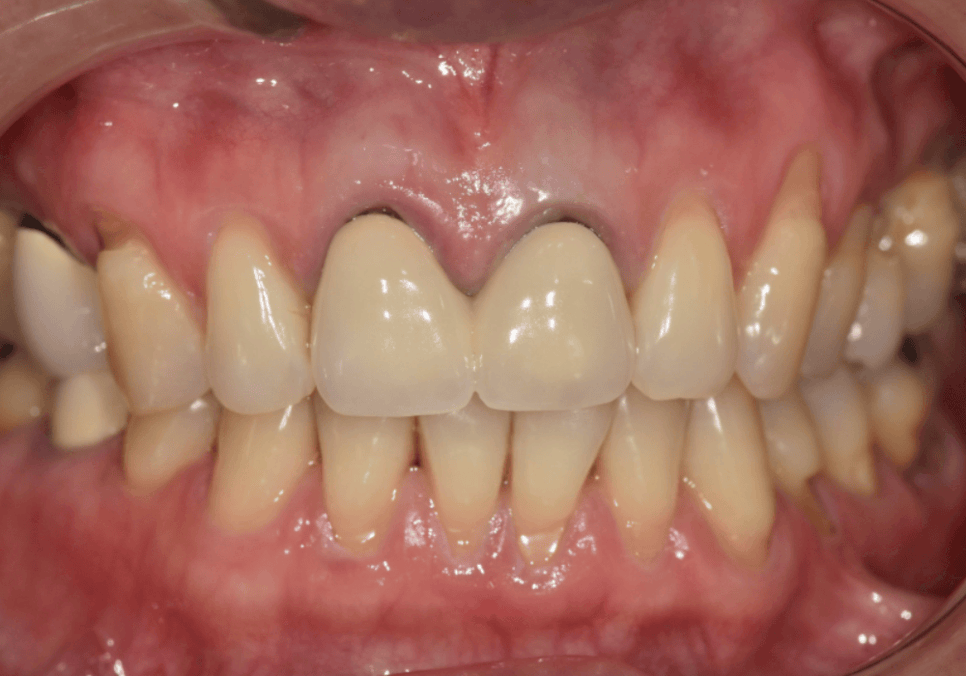

오래전 씌운 치아, 잇몸이 까매져 내원한

환자분 사례

잇몸 까매짐 원인,증상,치료 방법

이 환자분은 오래 전에

앞니 2개(#11, #21)와

윗니 어금니 1개(#15)에

PFM 크라운을 씌우셨다고 합니다.

250513

그런데 시간이 점점 지나면서

잇몸이 까매지더니

요즘엔 냄새까지 난다며

걱정스러운 표정으로 내원하셨습니다.